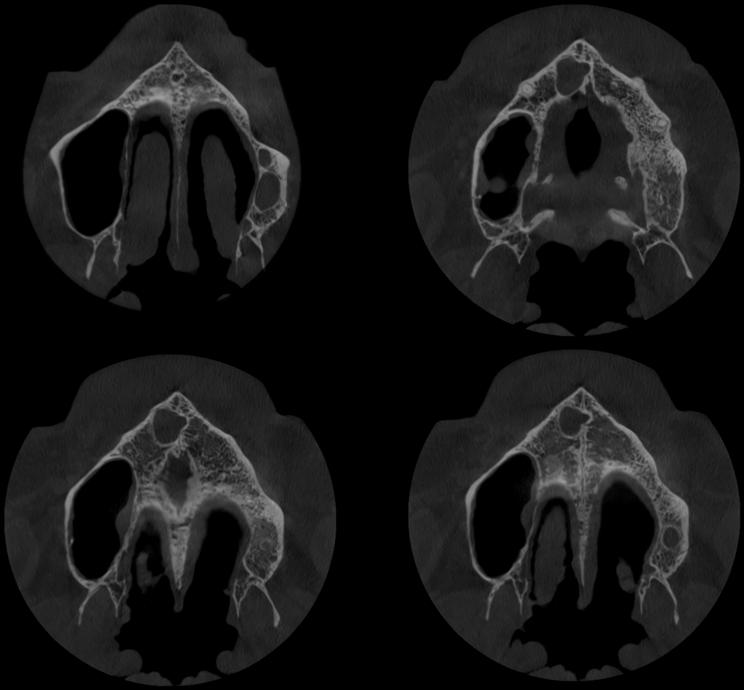

A la evaluación de la tomografía volumétrica (CBCT) en los cortes axiales (Figura 2) y transaxiales (Figura 3), se evidencia imagen hipodensa localizada hacia distal del conducto nasopalatino, de limites definidos, borde parcialmente corticalizados, que se extiende en sentido mesio distal de distal de pieza 12 hasta línea media, comprometiendo cortical de conducto nasopalatino.

CORTES AXIALES

CASO 336 - CORTES AXIALES - IDM